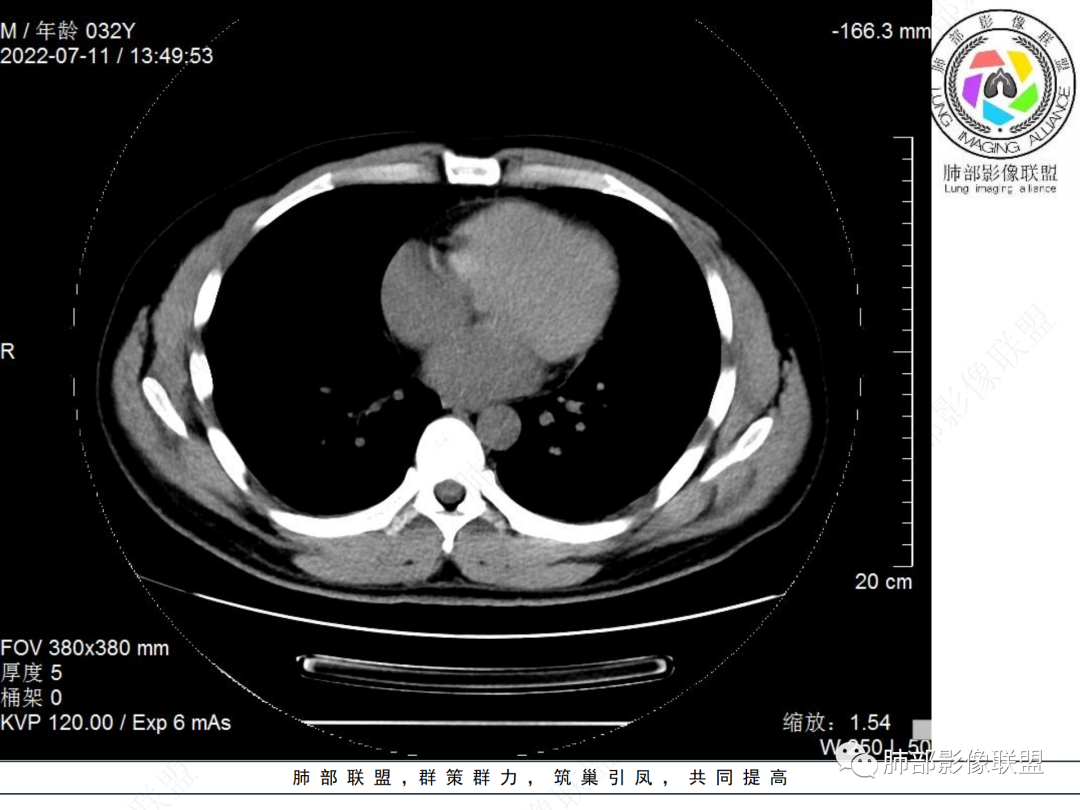

左肺下叶后基底段开口处结节,边缘光滑清楚,没有增强扫描,年轻男性患者痰血三天,考虑1.良性病变:腺瘤、错构瘤、平滑肌瘤

2.恶性:类癌、粘液表皮样癌。

左肺下叶外后基底段气管内见结节状影,边缘部分清晰。考虑错构瘤,待排恶性病变。

左肺下叶气管内外占位病变,咯血病史,考虑类癌,粘表待排。

青年男性,左肺下叶后基底段支气管开口软组织结节,边缘光整,气管镜提示质软,易出血,考虑类癌

左肺下叶后基底段开口处腔内见壁结节,花生米样,宽基底,补充增强及矢状位重建,确定我无向壁外突破浸润生长,另见强化的特点,临床触之易出血,类Ca可能性大。

年轻男性,咳血,左肺下叶后基底段支气管腔内结节,边缘光滑,首先考虑青年三件套,类癌大于粘液表皮样癌,支气管镜质软,触之易出血,鉴别血管瘤,平滑肌瘤

左肺下叶后基底段开口部结节,密度较均匀一致,边缘较光整,目测密度偏低,支气管镜示:质软、触之易出血,考虑恶性,类癌。

支气管腔内结节,有蒂与支气管壁连接,考虑良性病变可能性大,支气管错构瘤 血管瘤一类的

左肺下叶后基底段支气管腔内结节,有蒂,容易出血,先考虑良性病变,肉芽组织型血管瘤,与类癌鉴别。